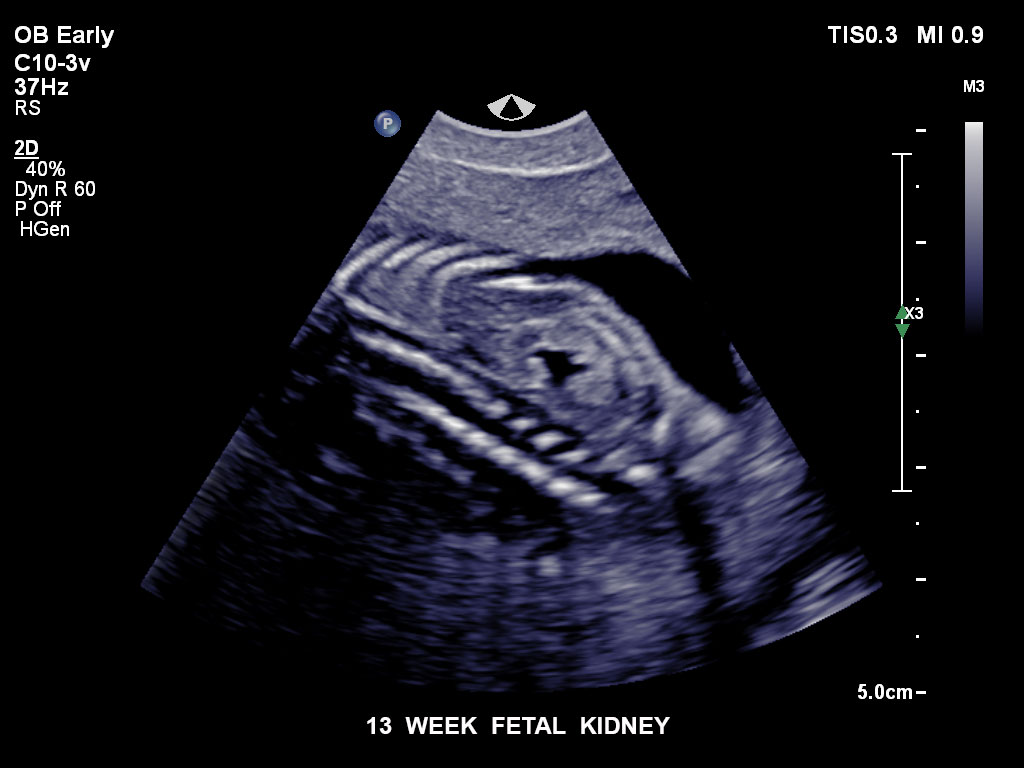

Bildgebung im 1. Trimenon

Überzeugende Bildgebung in allen Schwangerschafts­dritteln

Die EPIQ-Produktreihe mit ausgereiften Schallköpfen erfüllt die Anforderungen auch Ihrer anspruchsvollsten gynäkologischen Untersuchungen und während der gesamten Schwangerschaft.

• C10-3v PureWave-Breitband-Endo-Convex-Schallkopf, ideal für anspruchsvolle Myom- und komplexe Ovar-Untersuchungen sowie Bildgebung im ersten Schwangerschaftstrimester